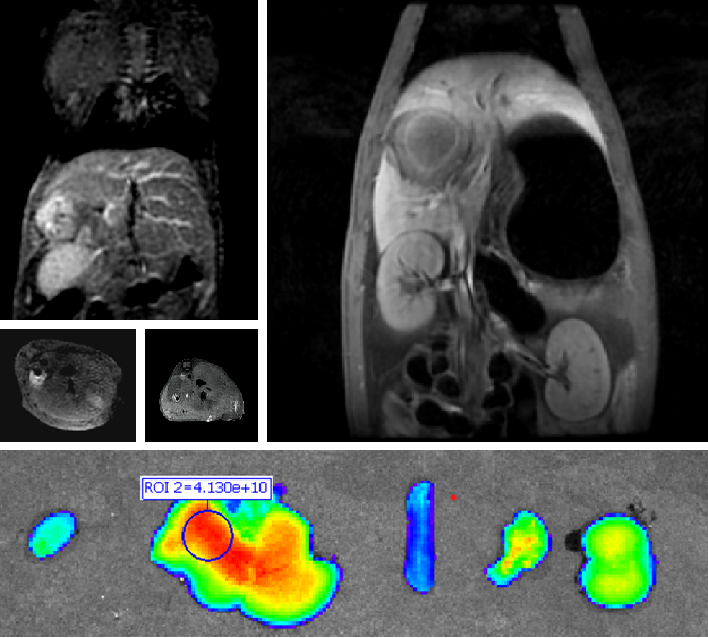

(二)适应症:本品拟用于原发性肝癌患者的术前诊断及术中导航。

PL002是浙江普利药业有限公司研发的荧光/磁共振双模态造影剂,开发荧光/磁共振双模态造影剂成为提高原发性肝癌手术效率的有效方案。双模态造影剂的荧光成像能力可用于肝癌术中荧光导航,而磁共振增强能力可用于在术前判断肝脏代谢能力,推测肿瘤及肝脏对造影剂的摄取情况,提高肿瘤诊断精度,降低术前规划难度。

PL002相较于吲哚菁绿具有明显优势。目前吲哚菁绿在临床使用中存在给药到手术时间不确定的问题,可能造成病灶与正常组织对比度不足,影响术中的病灶的判断,PL002采用独特的钆络合物与荧光分子共价键结合的分子结构设计,这种设计能够让医生在术前通过磁共振成像确定造影剂在病灶中的聚集情况,进而针对患者个体情况来对手术时间进行规划。同时,由于PL002体内更为稳定,在荷瘤小鼠模型中同等条件下荧光成像效果维持时间长于现有荧光造影剂,也保证了其在临床应用中具有更宽的手术窗口。